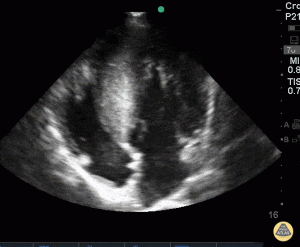

- Echocardiography4,11,14

- Assess LV size4,11,14

- Hypertrophy especially at septum with resulting obstruction and decreased LV size:

Courtesy of POCUS Atlas: https://www.thepocusatlas.com/pediatrics-1/3gcr6yneuyx87qxkx71bgsnkywqmi1

- Apical hypokinesis with basal hyperkinesis causing functional obstruction

- Look for a hyperdynamic LV with a very small ventricular cavity during systole

- SAM

- Poor LV filling and outflow obstruction in sepsis on vasopressors and inotropes with LVOTO:

Courtesy of Pocus Atlas: https://www.thepocusatlas.com/valvulopathy/left-ventricular-outflow-tract-obstruction - Mitral regurgitation (may be secondary to SAM)